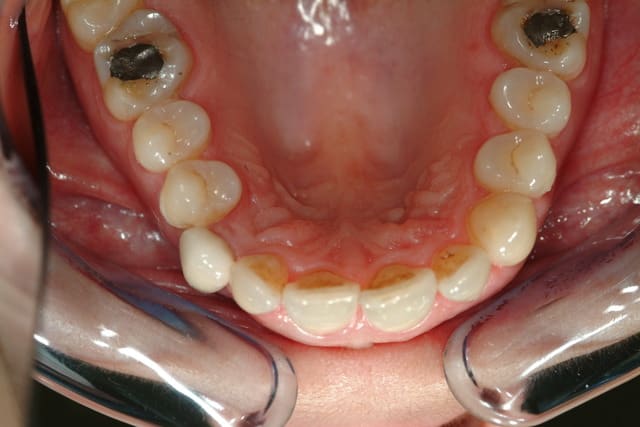

et la #46 aussi...

Pour la 13, c'est l'implant ou le pillier qui est visible ?

Type d'implant ?

Si c'est un hex externe, tu peux tailler un peu le buccal...

pillier métal avec céramique rose et couronne Zircone...

Céramik et bientôt la 36,

Il me semble que c’est le liserai du pilier qui est visible, que l’ajustage la couronne soit perfectible et que l’on aperçoive légèrement l’implant.

L’espace entre 12 et 14 est trop faible pour aligner la 13 qui est trop courte sur bord incisif.